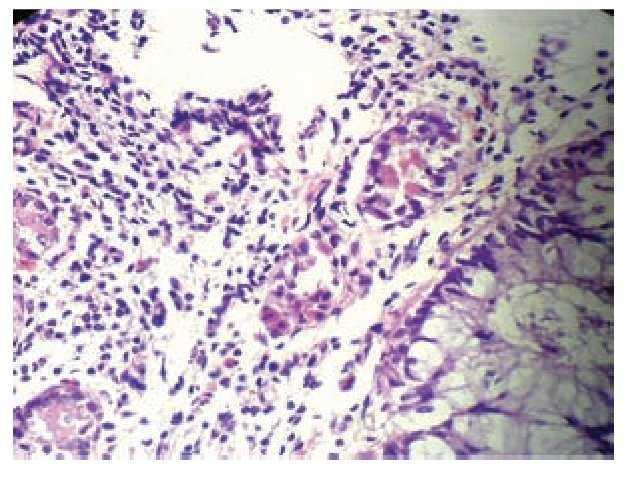

Se realizaron marcadores serológicos para virus de hepatitis B, virus de hepatitis C, virus de inmunodeficiencia humana, anticuerpos antinucleares, antimitocondriales y anticitoplasma del neutrófilo central y periféricos (VHB, VHC, HIV, ANAs, AAM, cANCA y pANCA) los cuales fueron negativos. El estudio de heces demostró sangre oculta ++++ y los coproparasitoscópicos seriados3 fueron negativos. Los siguientes estudios paraclínicos demostraron Tránsito intestinal: datos compatibles con malabsorción intestinal (Figura 1). Panendoscopia: pangastritis no erosiva leve, esofagitis aguda grado I (Savary-Miller), duodenitis leve. Las biopsias de duodeno mostraron infiltración eosinofílica y la colonoscopia demostró pancolitis e ileítis activa con erosiones lineales y eritema de la mucosa (Figura 2) con afección predominante en el íleon distal. Múltiples biopsias de íleon distal, hasta recto, con infiltrado eosinofílico predominante (>80%), en número de 18-22 células por campo de alto poder (Figura 3). Estudios complementarios confirmaron ausencia de eosinofilia periférica, niveles normales de IgE y ecocardiograma transtorácico normal.

Figura 3. Sigmoides 20X, lámina propia con infiltrado en 80% por eosinófilos, con zonas de erosión en el epitelio de superficie.